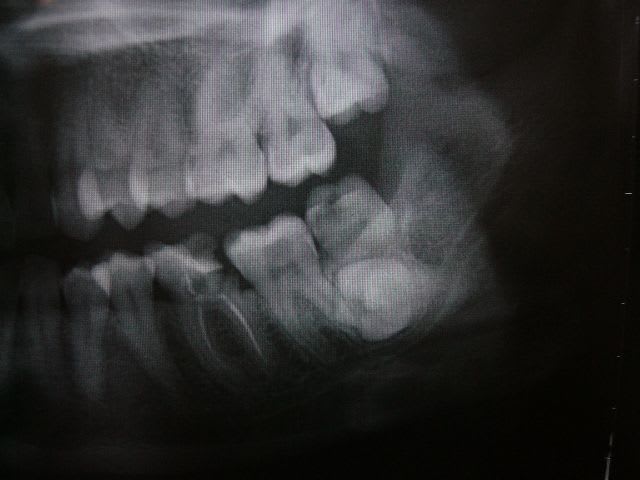

C’est un cas simple ou il faut juste stimuler un peu la croissance et reformer les arcades.

C’est le type même du traitement d’interception en denture mixte.

Pas de panique, petite DDM, bonne classe 2 sq,un peu de supracclusion ---> la laisser grandir un peu, et la confier à un ODF pour un peu de fonctionnelle et un alignement.

... elle est en classe I, avec une grosse supra.

TT "fonctionnel" prévu dans qqs semaines.

... c'est en cours ... un appareil de chez Rocky Mountain va être mis en place, à porter environ 16 heures/jour; il va falloir que je m'en fasse expliquer le principe lors de la séance de pose.